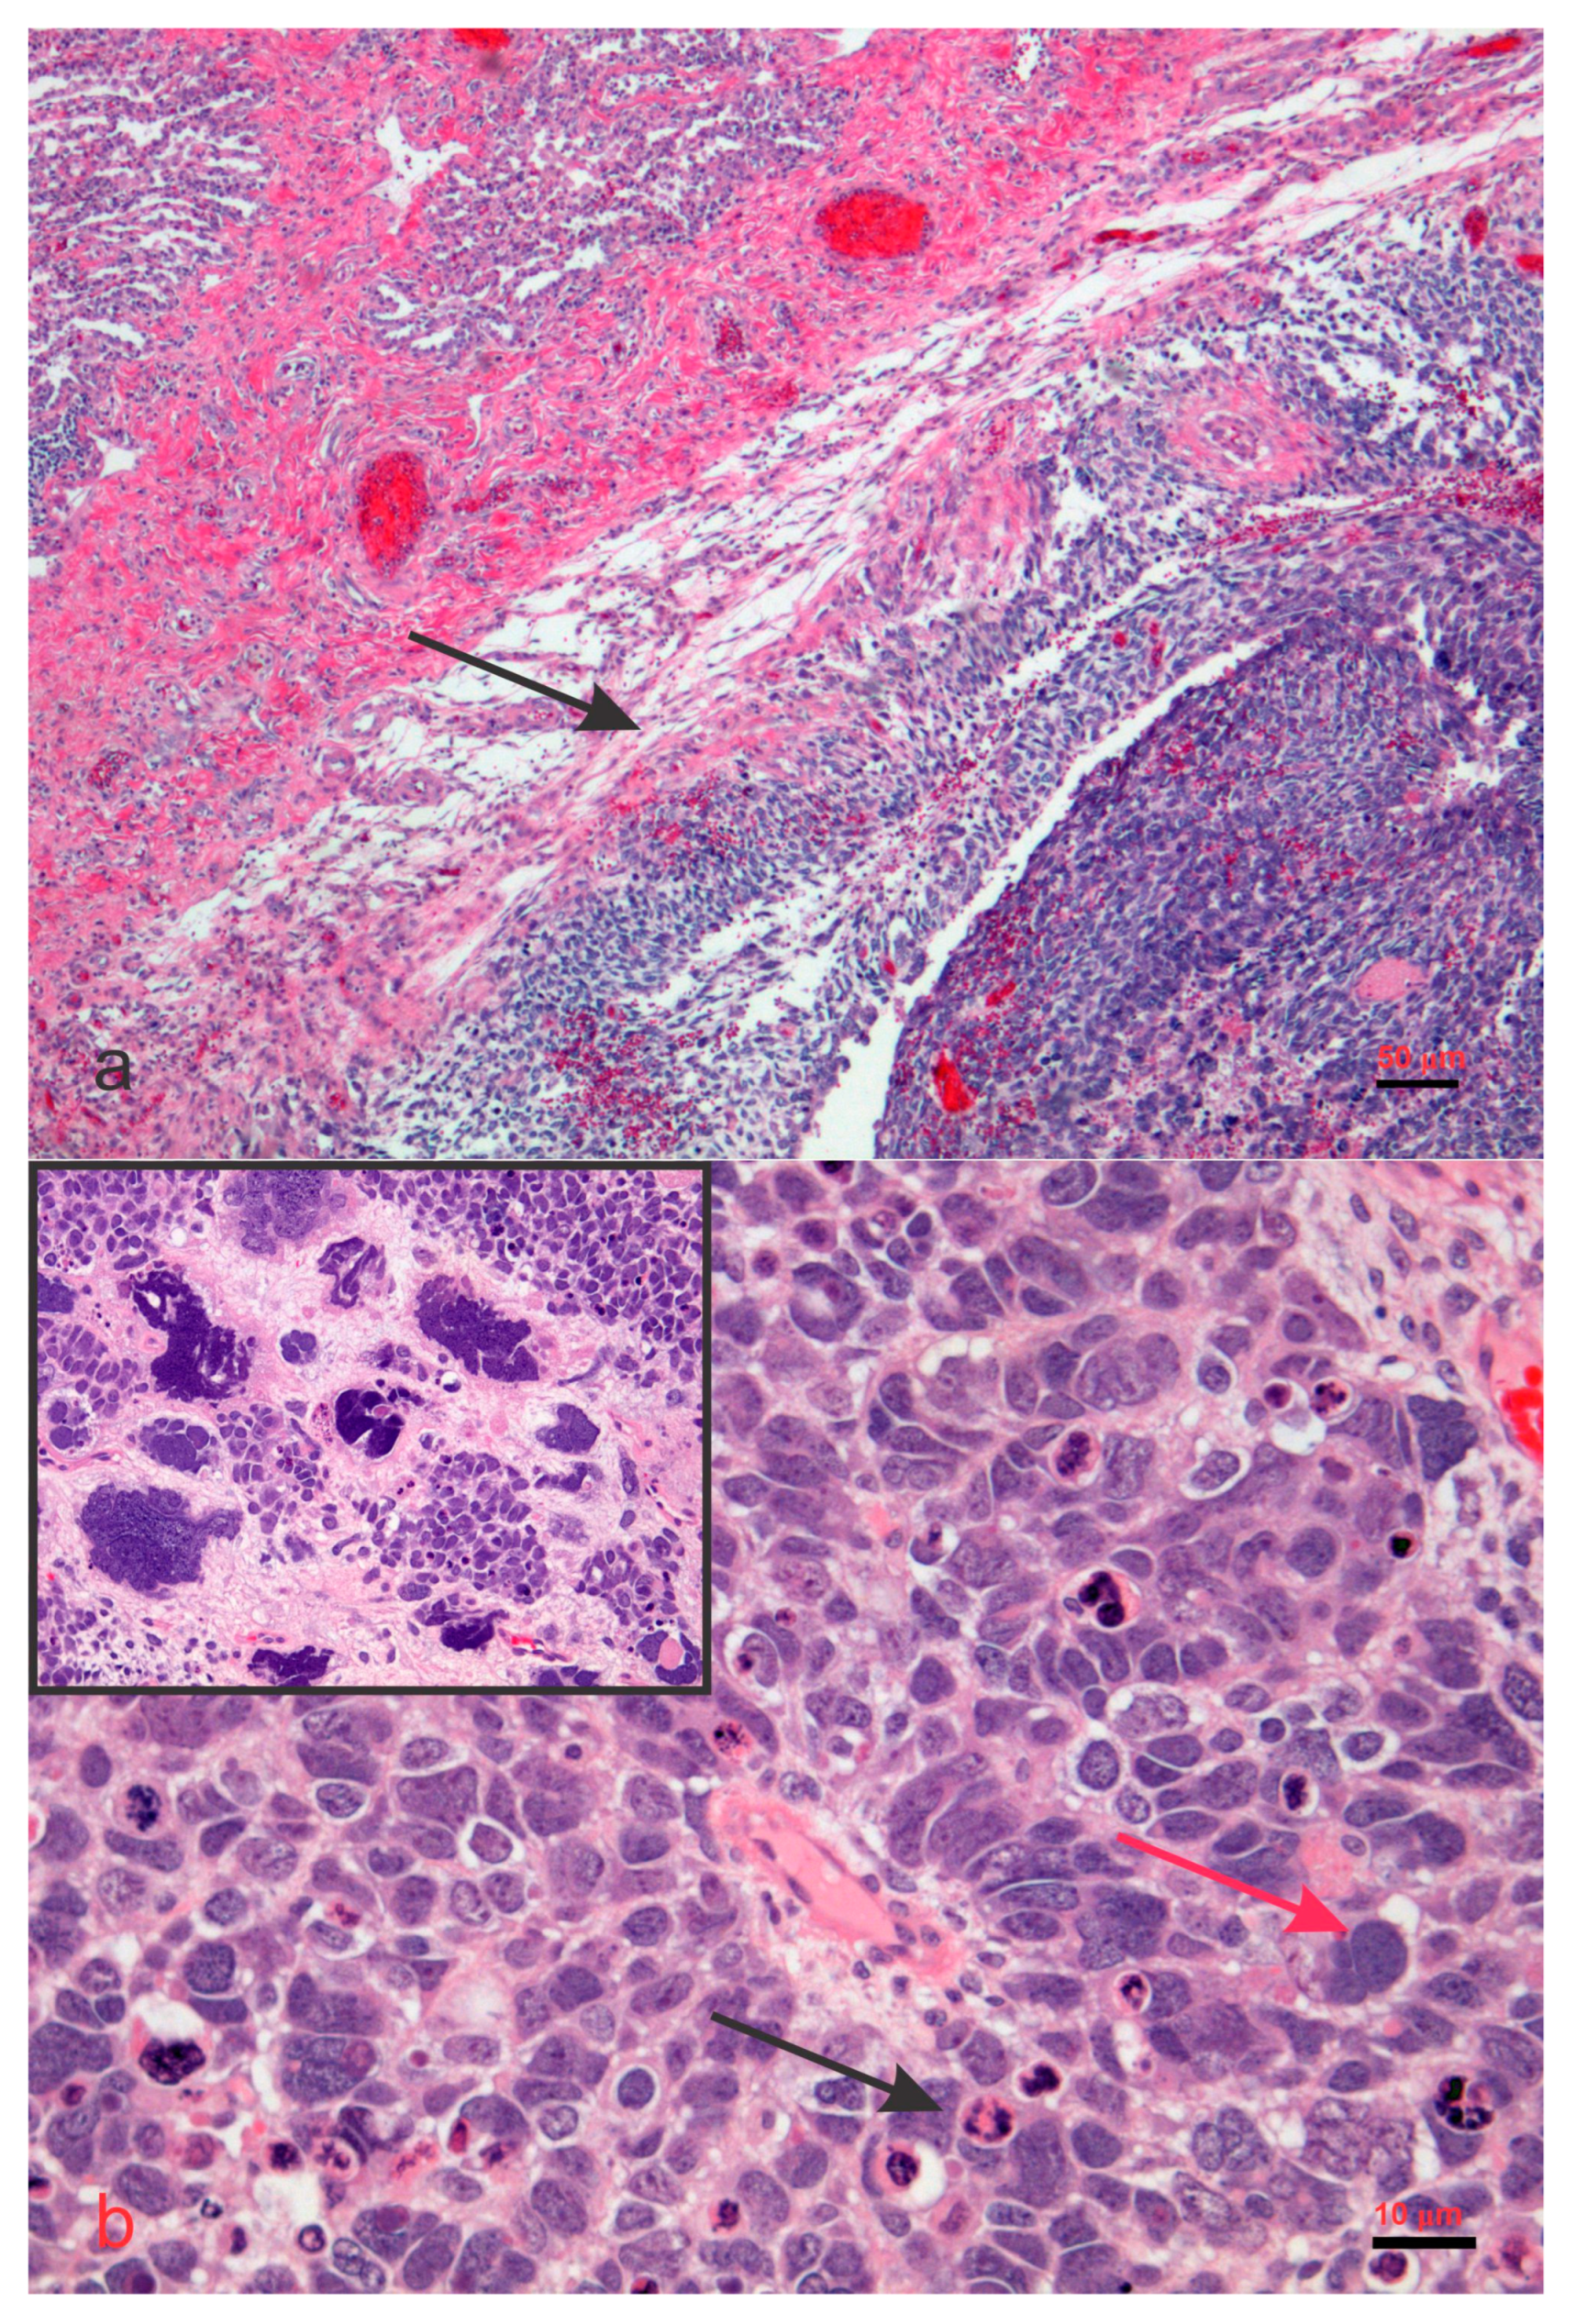

5. Disorders Associated with DICER1 Gene Mutations

6. DICER1 Syndrome